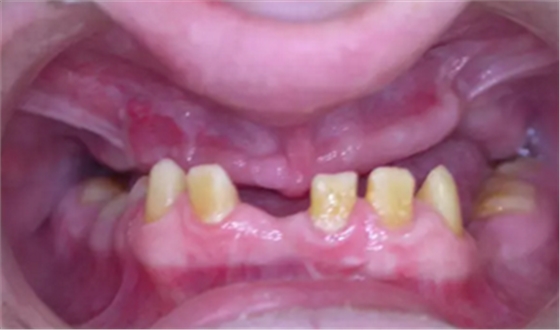

该患者 12 岁时已诊断为釉质发育不全。家族史正常,否认全身系统性疾病。全身系统检查无明显异常,检查双侧颞下颌关节、开口度正常。口内及 X 片检查见上颌缩窄,上颌牙列缺失,安氏三类错牙合,下颌牙牙冠短小,牙根正常。上颌大量牙槽骨因以前手术干预而丧失,后牙区牙槽骨高于前牙区。病变牙齿在之前的治疗中已被拔除。

图 4. 术前口内照